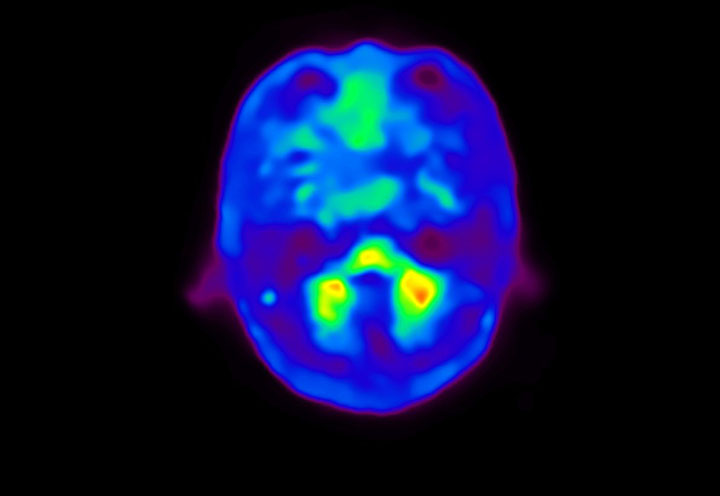

Axial